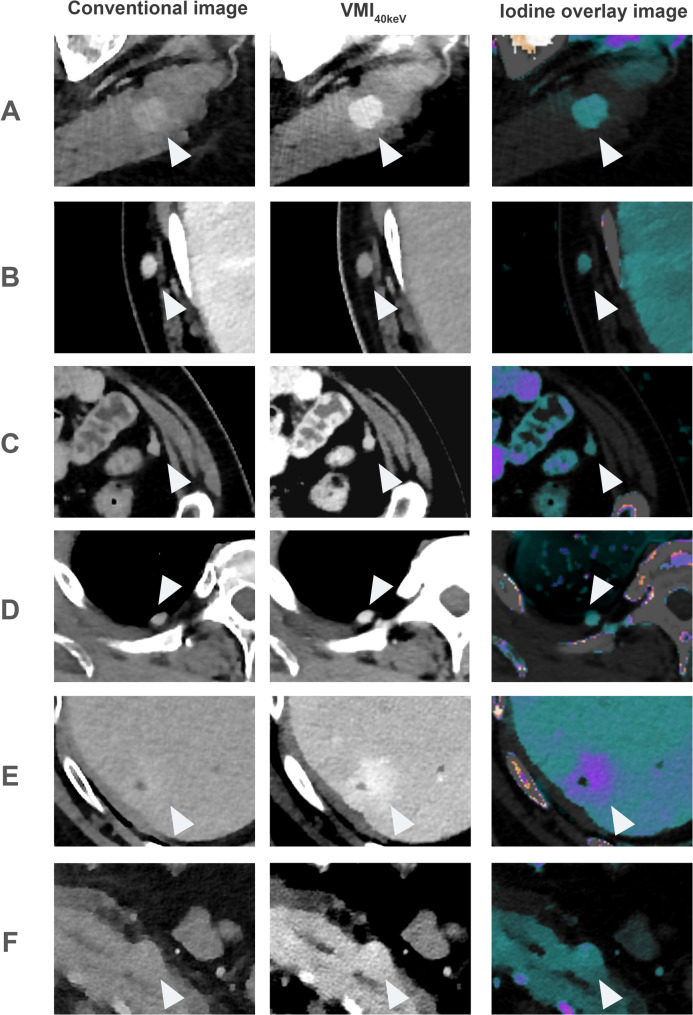

Methods: In total, 308 patients with melanoma, 95 patients with metastases and a control group of 213 patients without metastases, who underwent oncologic staging CT of the chest, abdomen and pelvis on a dual-layer dual-energy CT system (dlDECT) were retrospectively included. Conventional images (CI), color-coded iodine overlays (IO) and virtual monoenergetic images at 40 keV (VMI40keV) were reconstructed. 6 radiologists (3 experienced with 6 to 9 years and 3 less experienced with 2 to 4 years of experience) read all cases in a CI-based session, and a session based on a combination of CI, IO and VMI40keV. Readers were asked to determine presence of metastases in specific tissues in a binary fashion and to indicate diagnostic certainty and lesion delineation on 5-point Likert scales.

Results: Sensitivity for detection of metastases in the skeletal muscle and peritoneum was significantly higher for the spectral assessment (for skeletal muscle 70% vs. 61%; for peritoneum 76% vs. 62%, both: p < 0.05). For subcutaneous metastases, there was a significant increase in specificity (92% vs. 89%, p < 0.05), however accompanied with a significant decrease in sensitivity (79% vs. 85%, p < 0.05). Diagnostic certainty was rated significantly higher for spectral images than CI in all (6/6) of the assessed tissues, whereas improvements in lesion delineation were noted for the skeletal muscle, the subcutaneous tissue and the pancreas.

Conclusions: We found that in melanoma patients, the benefit of dlDECT-derived spectral reconstructions depends on the assessed tissue. While assessment of skeletal muscle and peritoneal metastases was significantly improved, low or absent iodine uptake of subcutaneous lesions led to false negatives and a consecutive decrease in sensitivity.